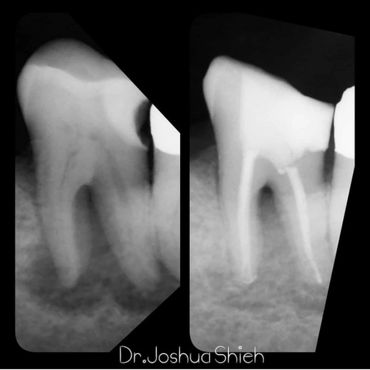

If the tooth is planned for extraction, an x-ray of the area will be taken to plan for the type of extraction.

Simple extractions are performed on erupted teeth that have regular anatomy (root and crown), and are not severely broken.

A surgical extraction is a more complex procedure. It is used if a tooth may have broken off at the gum line or has not come into the mouth yet. Surgical extractions are commonly performed by general dentists or oral surgeons depending on the case. Sometimes it’s necessary to remove some of the bone around the tooth or to cut the tooth in half in order to extract it. For surgical extractions, patients receive local anesthetic. A suture is usually required to control bleeding and facilitate healing.